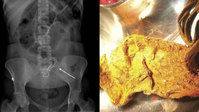

¡°¹ßµî¿¡ Àú°Í, ±Í¾ß?!¡± °øÀå ±â°è¿¡ ±Í À߸° Áß±¹ ¿©¼º¡¦ ¹«½¼ ¼ö¼ú ¹ÞÀº °É±î?

»ç°í·Î ¿ÏÀüÈ÷ ¶â°Ü³ª°£ ÇÑ ¿©¼ºÀÇ

±Í

¸¦ ¹ßµî¿¡ Àӽà À̽ÄÇØ »ì·Á³½ µÚ 5°³¿ù ¸¸¿¡ ÀçºÎÂø¿¡ ¼º°øÇÑ »ç¿¬ÀÌ ÀüÇØÁ³´Ù. Áö³ 10ÀÏ(ÇöÁö ½Ã°¢) ¿Ü½Å ¹Ì·¯¿¡ µû¸£¸é Áß±¹ »êµÕ¼ºÀÇ ÇÑ °øÀå¿¡¼ ÀÏÇÏ´ø 30´ë ¾§¾¾´Â ¸Ó¸®Ä«¶ôÀÌ °øÀå ±â°è¿¡ »¡·Á µé¾î°¡¸é¼ ¿ÞÂÊ

°¡ ¶â°Ü³ª°¡´Â »ç°í¸¦ ´çÇß´Ù. »ç°í Á÷ÈÄ º´¿øÀ» ã¾ÒÁö¸¸

ÁÖº¯ÀÇ Ç÷°ü°ú ½Å°æ ¼Õ»óÀÌ ³Ê¹« ½ÉÇØ Áï½Ã Á¦ÀÚ¸®¿¡ ºÙÀÌ´Â °ÍÀº ºÒ°¡´ÉÇß´Ù.